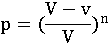

- доза, вызывающая гибель 50% животных

- доза, вызывающая гибель 50% животных